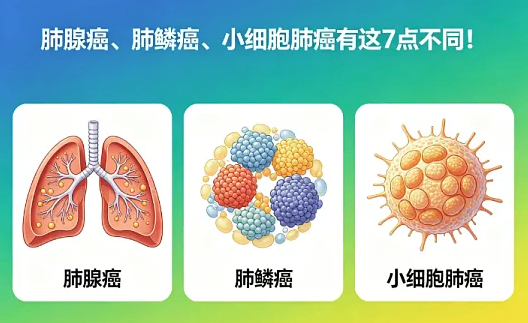

肺癌:发病率最高,小细胞癌最凶险

肺癌是国内发病率最高的癌症,不同类型复发风险差很多。小细胞肺癌长得快、转移早,很多患者术后半年到一年就复发;肺腺癌里有微乳头成分的,还有术后病理提示脉管有癌栓、胸膜侵犯、淋巴结转移的,复发风险也明显升高。

术后别只拍胸片,一定要做低剂量螺旋 CT,看得更清楚。还要根据病理分期和基因检测结果,该做辅助化疗、靶向或免疫治疗的,一定要坚持做完,别因为怕副作用就放弃。